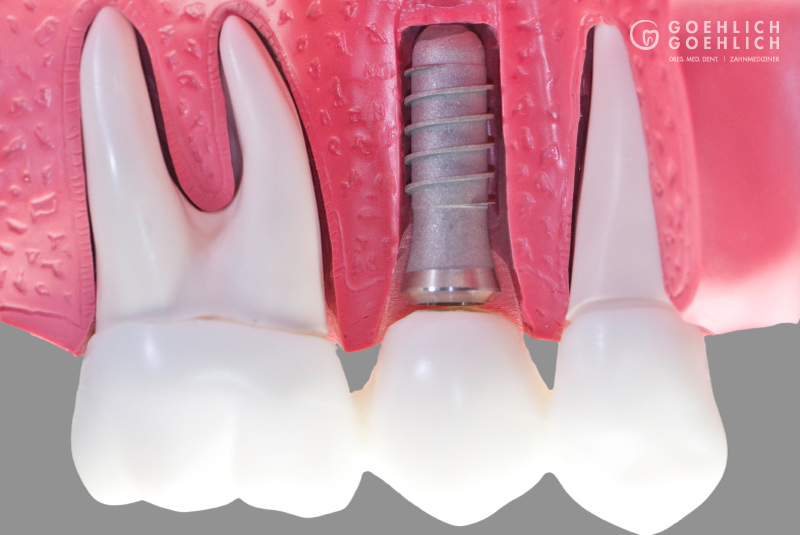

Als Implantat bezeichnet man in der Zahnmedizin eine künstliche Zahnwurzel, die nach Verlust eines eigenen Zahnes als Ersatz eingebracht wird. Das Implantat dient als Basis bzw. Verankerung einer festsitzenden Krone. Geht nur ein Zahn verloren, dient das Implantat zum Schluss der Lücke, ohne dass eine Brücke angefertigt werden muss und dafür die vielleicht intakten Nachbarzähne abgeschliffen werden. Damit schonen wir die umgebenden Zähne. Spätfolgen des Zahnverlustes, wie Kiefergelenkprobleme, Zahnwanderungen oder Karies können vermieden werden. Sind bereits mehrere Zähne verloren gegangen, die nur durch eine Teil- oder Vollprothese ersetzt werden können, ermöglichen wir durch das Einbringen mehrerer Implantate wieder einen festsitzenden Zahnersatz.

Implantate bestehen aus dem körperverträglichen und langlebigen Metall Titan. In einem minimalinvasiven operativen Eingriff setzen wir das Implantat in den Knochen ein. Die speziell bearbeitete Oberfläche garantiert ein zügiges Einheilen und das feste Verwachsen mit dem umgebenden Knochengewebe. Implantate können darüber hinaus den gefürchteten Knochenschwund in zahnlosen Kieferabschnitten verhindern oder verzögern. Den eigenen Zahnwurzeln ähnlich, übertragen Implantate die Kaukräfte auf den Kieferknochen. Dieser Trainingseffekt ist ein wichtiger Reiz für den Erhalt des Knochen- und Stützgewebes. Deshalb sollten Implantate möglichst bald nach dem Verlust oder Entfernen eines Zahns verankert werden.